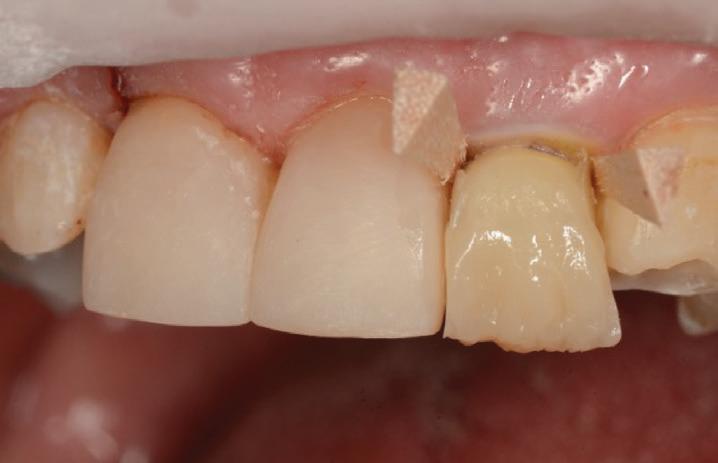

The teeth were cleaned of plaque and the chipped and unsupported enamel was removed (Figs. 4, 5). Fine bevels were placed to facilitate composite adhesion.

Small, 1/2 round bur undercuts were placed, and all of the exposed

dentine (and the old crown) were micro-etched with the Rondoflex 360 sandblaster, using 27um particles (Figs. 6, 7).